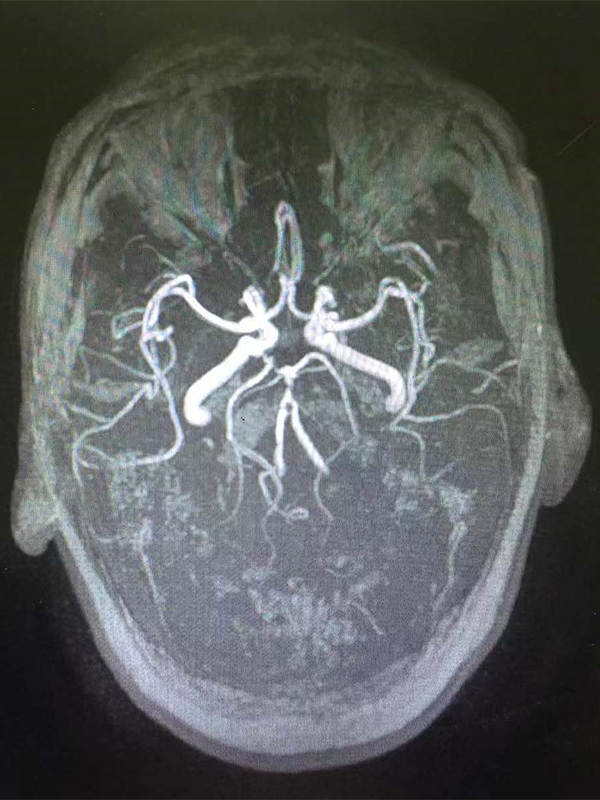

CT( 10) CT( 11 )

12 MRA